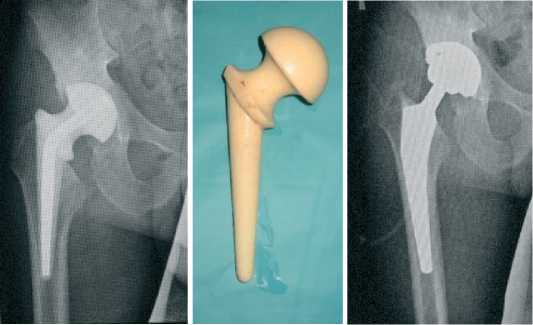

В качестве альтернативного варианта приводим пример случая двухэтапного эндопротезирования тазобедренного сустава при септическом стафилококковом коксите с использованием цементного спейсера, изготовленного интраоперационно с отливанием его компонентов в силиконовых формах.

а

б в

г д е

Рисунок 2 . Случай двухэтапного эндопротезирования тазобедренного сустава у больной М, 46 лет с деструктивной формой правостороннего септического коксита с использованием интраоперационно изготовленного спейсера: а – рентгенограммы больной перед операцией;

б - интраоперационное двухэтапное формирование анатомически адаптированного артикулирующего цементного спейсера в силиконовых формочках на 1-ом этапе хирургического лечения; в - рентгенограммы тазобедренного сустава с установленным спейсером; г - внешний вид удаленного цементного спейсера на 2-м этапе хирургического лечения; д - рентгенограммы тазобедренного сустава с установленным эндопротезом.